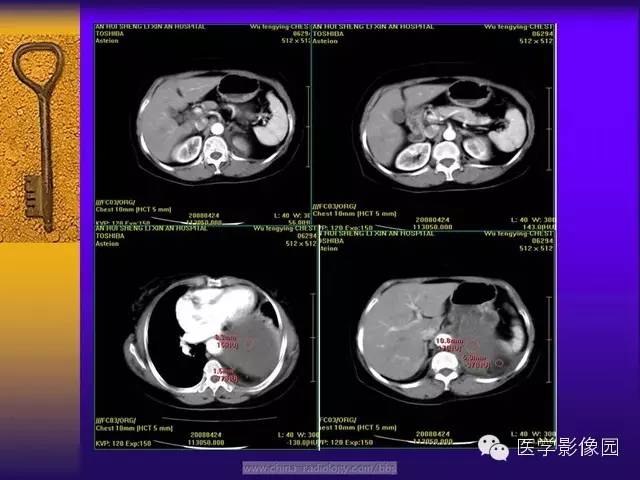

CT 平扫肿瘤密度以不均匀居多,肿瘤体积较小时密度可较均匀,随着肿瘤体积的增大其内部或周边可出现大小不等的低密度区,肿瘤越大坏死囊变的区域越大,形态越不规则。这与肿瘤细胞、胶原纤维的分布及二者发生玻璃样变、黏液样变及坏死囊变有关。肿瘤的供血血管由边缘向肿瘤内部延伸,肿瘤中心易出现血供不足而出现坏死、囊变。肿瘤越大坏死囊变的区域越大,形态越不规则。

增强扫描,动脉期肿瘤的周边强化明显并见多支供血动脉显影的“地图样”强化,静脉期瘤体呈现明显不均匀强化,这与肿瘤内的细胞密集区富有薄壁的“鹿角状”分支血管密切相关。肿瘤的血管丰富区、细胞密集区强化明显,强化早期肿瘤的供血血管从肿瘤的边缘向肿瘤内部沿伸,因此,强化早期瘤内迂曲血管影显示清晰;细胞稀疏区、胶原纤维密集区、黏液变性强化相对较弱,呈现静脉期强化,坏死囊变区始终未见强化。由于SFT的病理学表现多样,因此其增强后可出现多种强化形式,动脉期肿瘤内可见迂曲的供血血管由肿瘤边缘向肿瘤内部延伸,静脉期进行性强化对于诊断及鉴别诊断具有重要意义。